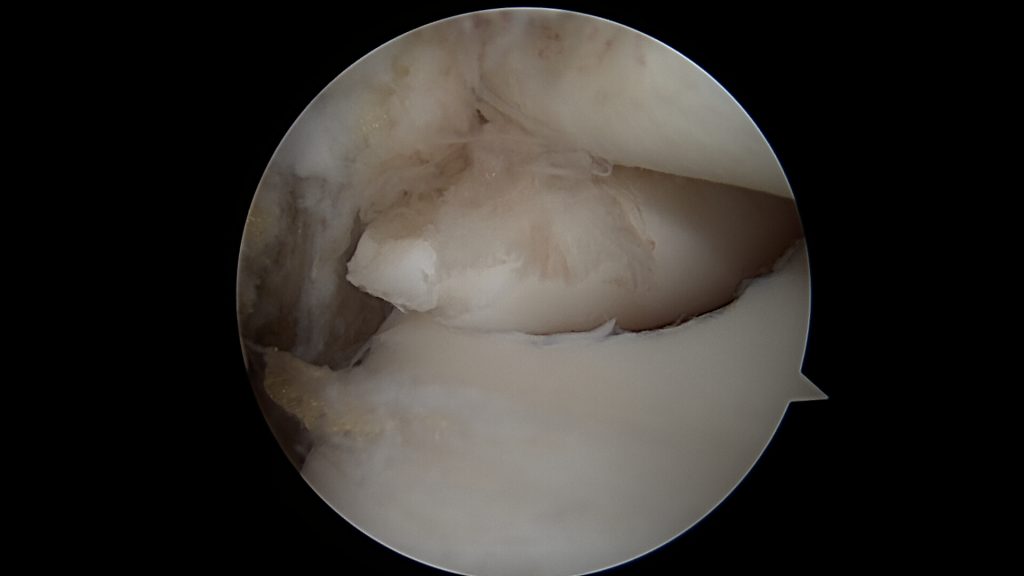

Uszkodzenia pełnej grubości chrząstki stawowej, punktowe wymagają leczenia operacyjnego. Nawet niewielkie pęknięcie chrząstki stawowej powoduje wtłaczanie płynu stawowego pod powierzchnie chrząstki oraz tworzenie się pod nią torbieli. Zwiększone ciśnienie oraz torbiele powodują następnie niszczenie kości oraz zapadanie się powierzchni chrzęstnej. Z czasem fragment chrząstki wraz z kością (uszkodzenie typu OCD) odrywa się i może przemieszczać się w jamie stawu.

Leczenie operacyjne polega na oczyszczeniu oraz odświeżeniu dna ubytku oraz wypełnieniu go materiałem Hyalofast, dedykowanym do uszkodzeń chrzęstno-kostnych. W niektórych przypadkach (młody wiek oraz duża wielkość fragmentu) możliwe jest ponowne przytwierdzenie wydzielonego fragmentu chrzęstno-kostnego OCD, jeśli nie uległ on wcześniej zniszczeniu.